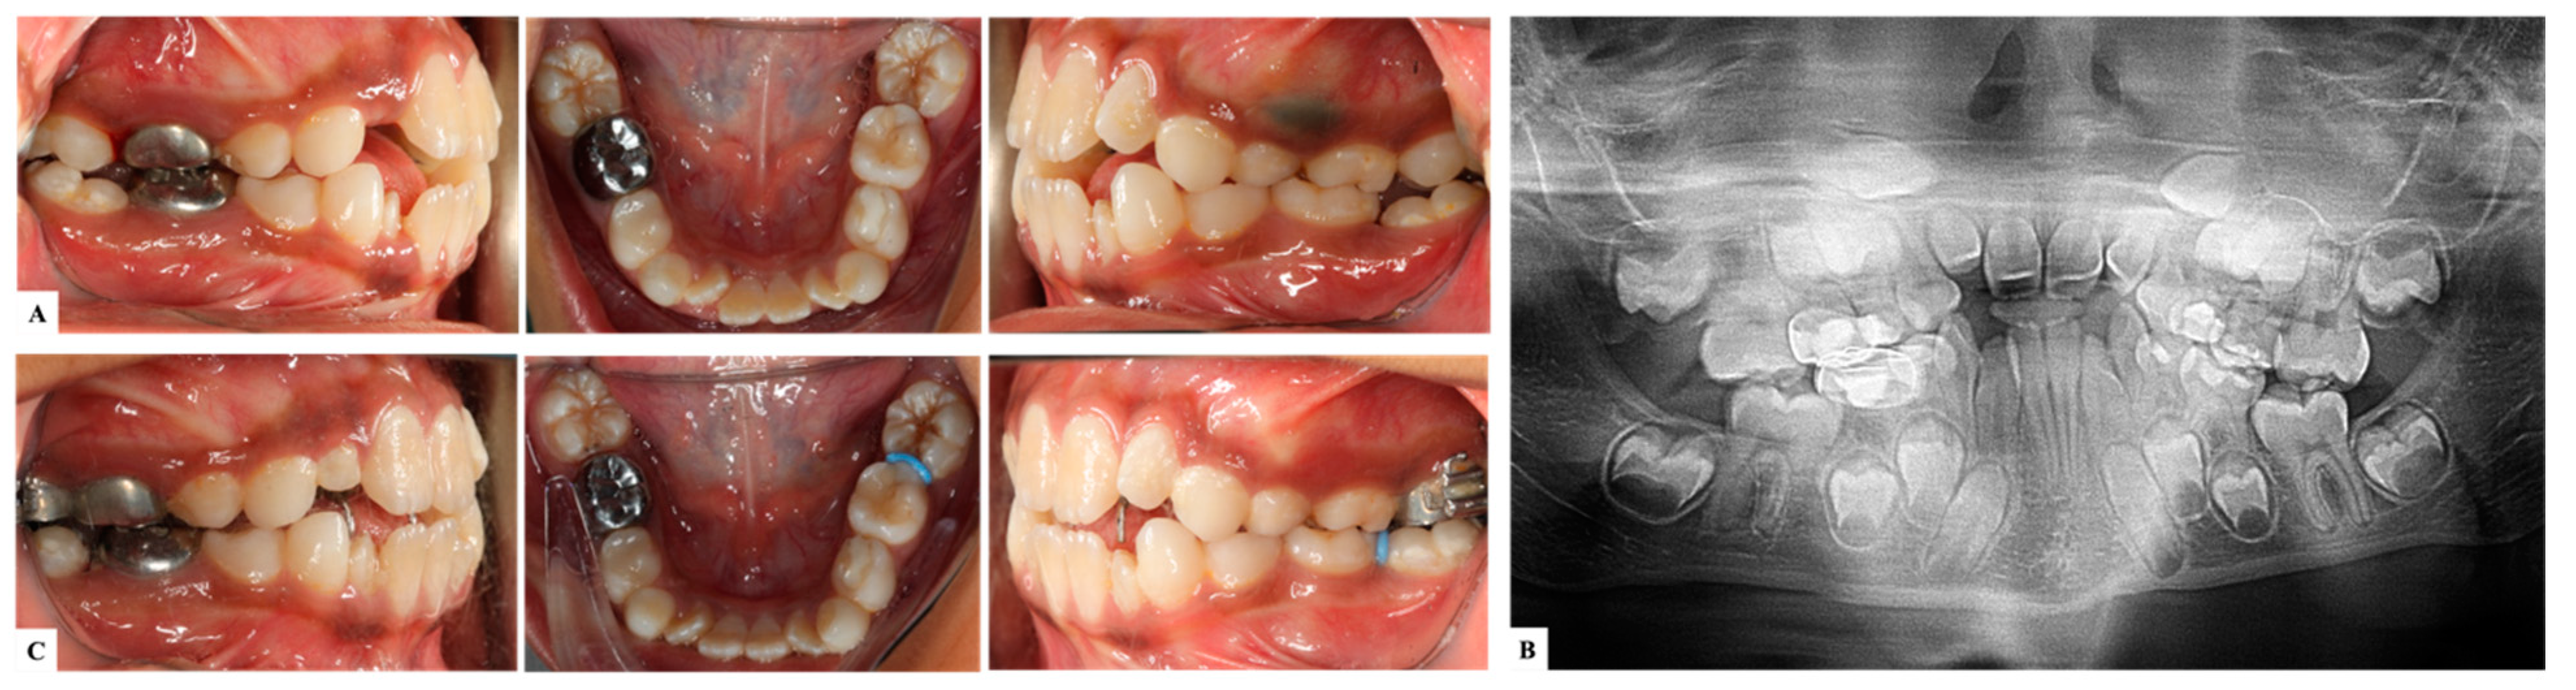

| Barberia-Leache ’s Classification (Based on the effect on second primary molar) * | |||||

| Grade 1 Mild | Grade 2 Moderate | Grade 3 Severe | Grade 4 Very severe | ||

| Limited resorption to the cementum or with minimum dentine penetration | Resorption of the dentine without pulp exposure | Resorption of the distal root leading to pulp exposure | Resorption that affects the mesial root of the second primary molar | ||

![]() | ![]() | ![]() | ![]() | ||

| Harrison and Michal’s Classification (based on severity of the lock using bitewing radiograph) * | |||||

| Normal | Minimal lock | Severe lock | |||

| No sign of impaction | Impacted less than half the width of the distal marginal ridge of the second primary molar | Impacted more than the width of the distal marginal ridge of the second primary molar | |||

![]() | ![]() | ![]() | |||